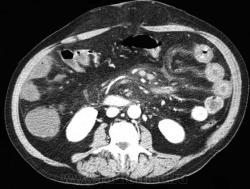

Осложнённая форма (чаще всего в результате странгуляции):

Для странгуляции тонкой кишки характерны утолщение стенок кишечника, васкулярные нарушения и выраженные патологические изменения в брыжейке и в брюшной полости. Диагностические находки включают в себя:

-расширенные петли тонкого кишечника проксимальнее транзиторной зоны (зоны обструкции).

-спавшиеся петли кишечника дистальнее уровня обструкции.

-транзиторная зона

-смешанный характер стаза содержимого кишечника в расширенных петлях, с преобладанием жидкостного компонента.

-утолщение стенки кишки циркулярного типа. Важно помнить, такой тип утолщения стенок тонкой кишки при непроходимости как правило связан с сосудистыми нарушениями.

-нарушение нормального контрастного усиления стенок кишки. Изменения варьируют от гиперконтрастирования до полного отсуствия контрастного усиления. Различные варианты этих изменений между описанными выше крайностями могут наблюдаться одновременно в разных сегментах тонкого кишечника. Полное отсутствие усиления означает артериальный рефлекторный спазм и свидетельствует в пользу тяжести поражения.

-петля с утолщенными стенками теряет свою эластичность и становится ригидной, вытянутой.

-пристеночный пневматоз тонкого кишечника, в особо тяжелых случаях появляются интрамуральные пузырьки газа.

-появление патологических плотностей в брыжейке, в виде распространяющихся матовых инфильтратов и тяжистости, за счет кровоизлияний в жировые ткани.

-застойные изменения сосудов брыжейки. Сначала диаметр сосудов увеличивается, но, со временем, наступает рефлекторный артериальный спазм, брыжейка будет выглядеть с обеднённой васкуляризацией. Сосуды сужены или с полностью коллабированным просветом.

-газ в просвете верхней брыжеечной вены.

-газ в просвете портальной вены.

-при заворотах нарушается нормальная сосудистая анатомия брыжейки. Сосуды как бы закручиваются вокруг оси заворота и тянут за собой изменненый брыжеечный жир, по типу раковины улитки или торнадо. Для большей наглядности, представьте себе кусок расправленной ткани на столе, которую вы прижали пальцем и начали закручивать не отрывая ваш палец от стола. На КТ сканах часто можно увидеть характерный признак конусовидной спирали (whirl sign).

-свободная жидкость в карманах брыжейки и в брюшной полости. Иногда жидкость может быть повышенной плотности за счет геморрагического компонента.

Различные примеры странгуляционной осложнённой непроходимости с характерными изменениями в брыжейке, внутрибрюшинном жире, утолщением стенок тонкого кишечника и нарушением контрастного усиления

Закручивание сусуда при завороте